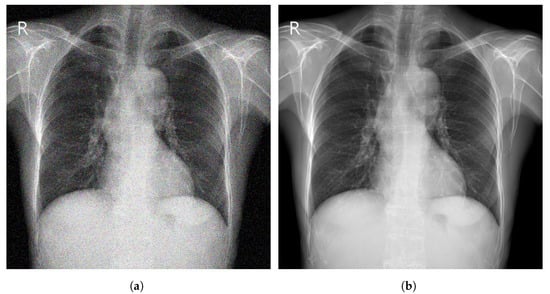

- CheXpert [44] is a large Public dataset of CXR images composed of 224,316 images acquired from 65,240 patients. It contains 14 common chest abnormalities, and it was collected from the Hospital of Stanford between 2002 and 2017. Each image in CheXpert dataset was labeled for the presence of 14 abnormality as negative, positive, or uncertain based on an automated rule-based labeller to extract the observations of experts from the free text radiology reports. Samples of CXR images from CheXpert are shown in Figure 3.

Figure 3.

Samples of CXR images from CheXpert dataset [44] where, (a) Atelectasis; (b) Cardiomegaly; (c) Edema; (d) Pneumonia.